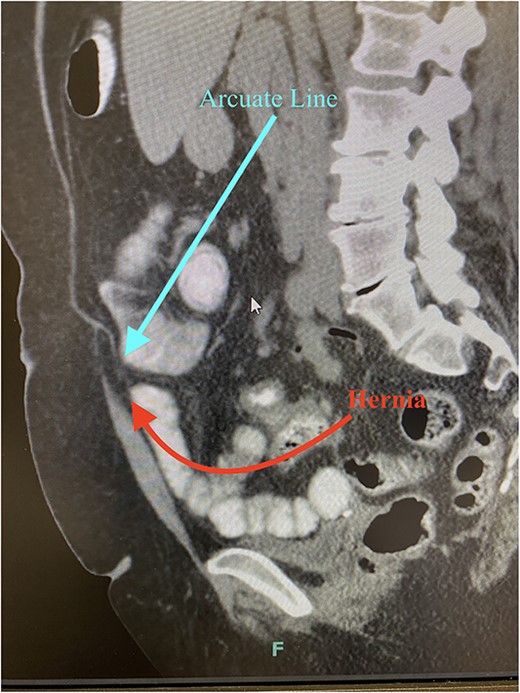

Arcuate line hernias are rare and are often misdiagnosed or found incidentally during laparoscopy. They may be completely asymptomatic. They may also present as an obscure cause of vague, intermittent abdominal pain. Reports of acute incarceration or strangulation are rare in the literature, likely due to the large hernia orifice. Diagnosis can be made on preoperative imaging. CT imaging demonstrates separation of the posterior sheath from the rectus abdominis at the arcuate line with herniated fat or viscus and is best seen on sagittal imaging (Fig. 6).

CT imaging demonstrates separation of the posterior sheath from the rectus abdominis at the arcuate line with herniated fat or viscus (sagittal imaging).